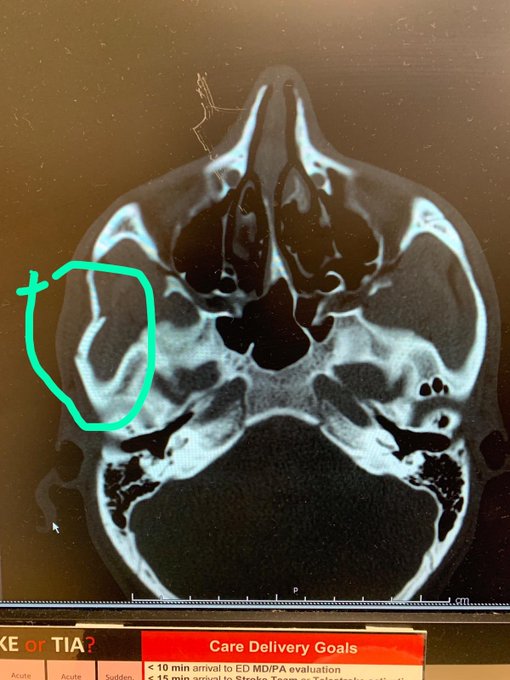

Primero, el libio de 27 años mostró la radiografía craneal que muestra una fractura en el sector derecho de su cabeza y luego compartió una fotografía en el que se le ve una parte hundida en el lado derecho del rostro.